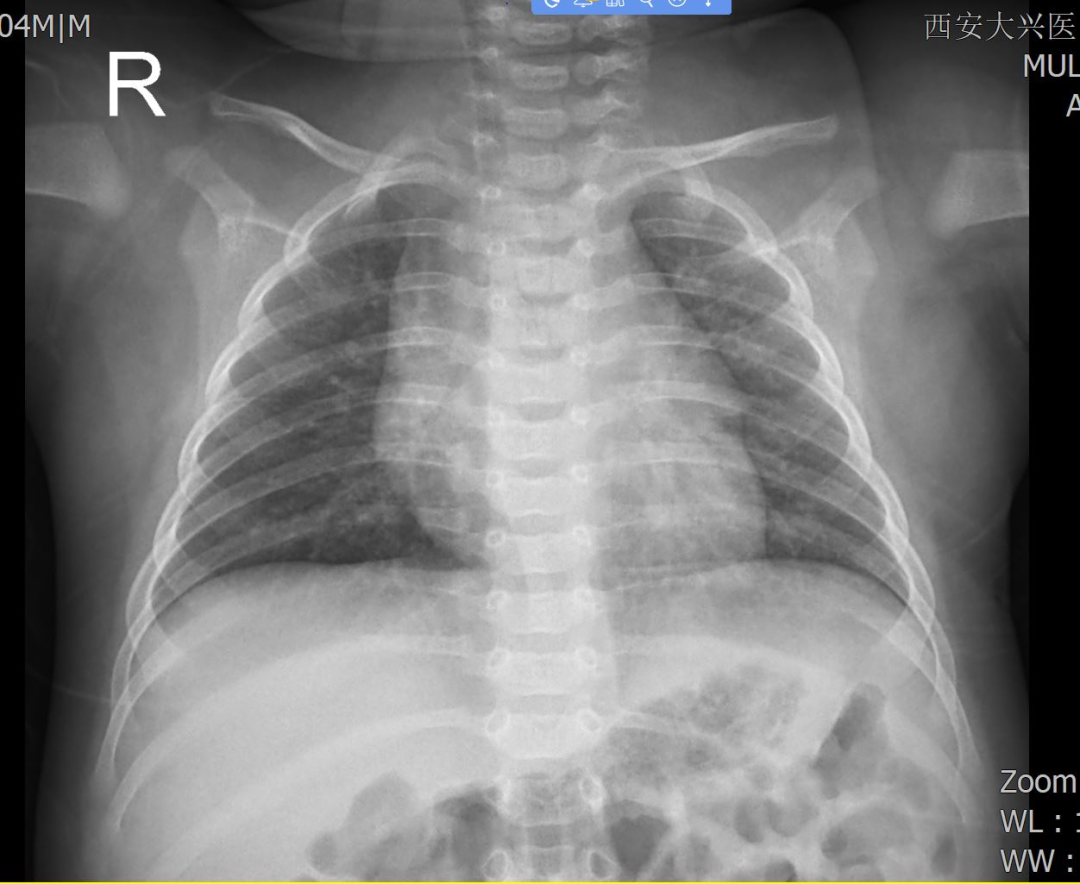

影像检查可见安安双肺纹理明显,考虑支气管肺炎最初根据症状和检查结果,医生诊断安安为支气管肺炎和腹泻病,并给予相应药物治疗。然而用药几日后,安安的症状仍未明显缓解。复查报告显示,安安的炎症指标虽“正常”却藏玄机:血常规、炎性指标均无明显异常,但肺部超声显示“双肺局部胸膜线增粗、散在B线,肺评分5分”,提示肺部损伤。于是,儿科王玲主任立即组织呼吸内科、麻醉二科会诊,与家属沟通后决定启动支气管镜检查。在儿童诊疗领域,支气管镜检查是一项极具挑战性的操作,尤其对于仅 4个月大的婴幼儿而言,更是难上加难。小患者气道纤细